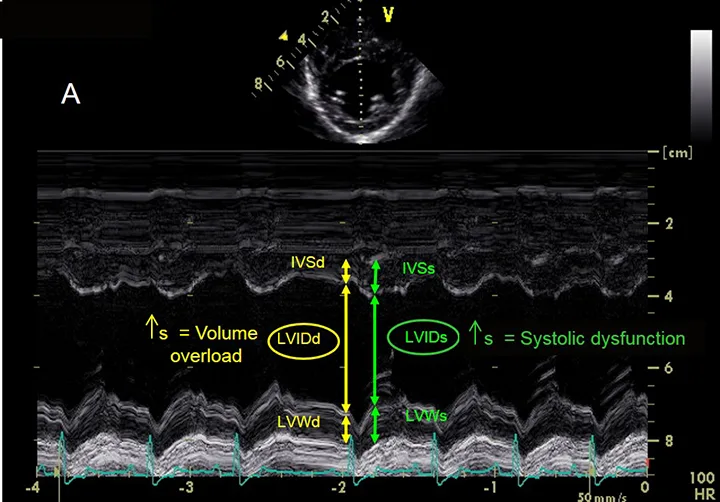

Figure 3A

Left ventricular measurements using M-mode echocardiography. During both systole and diastole, this image demonstrates interventricular septum thickness (IVSs, IVSd), left ventricular (LV) internal dimension (LVIDs, LVIDd), and LV free wall thickness (LVWs, LVWd). Increased LVIDd causes left ventricular volume overload, whereas increased LVIDs results in systolic dysfunction.

• Left ventricular (LV) internal dimension during systole and diastole (LVIDs, LVIDd)

• Interventricular septum thickness in systole and diastole (IVSs, IVSd)

• LV free wall thickness in systole and diastole (LVWs, LVWd)

• End-diastolic measurements are made at the onset of the QRS complex and end-systolic measurements at the smallest internal dimension.

• LV dimensions and wall thicknesses should be made at the level of the chordae tendineae or the tips of the papillary muscles just below the mitral valve tips. Normal values for standard LV measurements are reported for dogs (based on weight and some breeds) and cats.